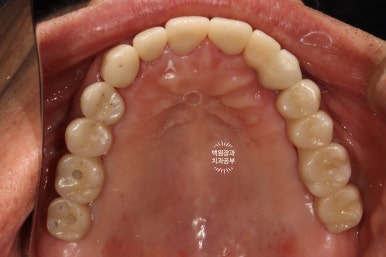

구강내 교합면 사진입니다.

모든 치아가 지르코니아 크라운으로 제작되어, 진짜 자연치같은 형태를 재현해내고 있습니다.

지르코니아 크라운운 캐드캠으로 제작되기 때문에 상당히 자연치와 유사한 형태와 색감을 냅니다.

임상적으로 아주 만족스러운 결과네요.